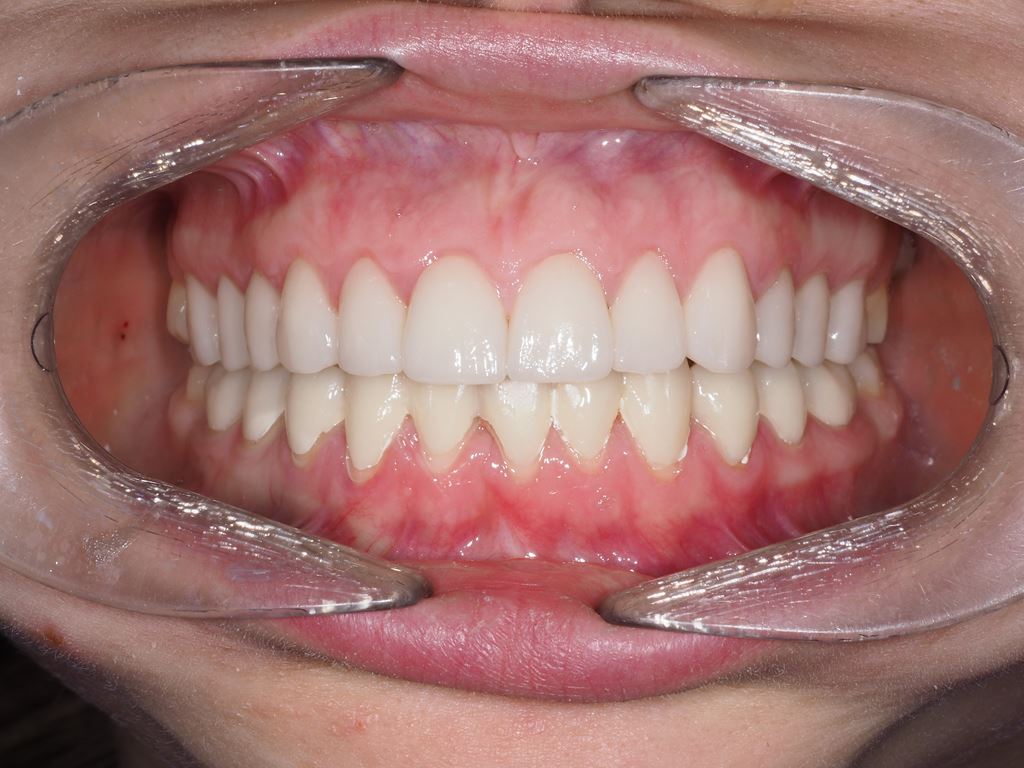

W pierwszym etapie diagnostycznym wykonano zdjęcia zewnątrz- i wewnątrzustne (ryc. 1-12).

Bezpośrednio po usunięciu zębów rozpoczęto leczenie ortodontyczne, które trwało 15 miesięcy i pozwoliło na uzyskanie zaplanowanych wcześniej pozycji zębów (ryc. 22-24).

Ryciny 39-50 przedstawiają stan po zakończeniu leczenia.